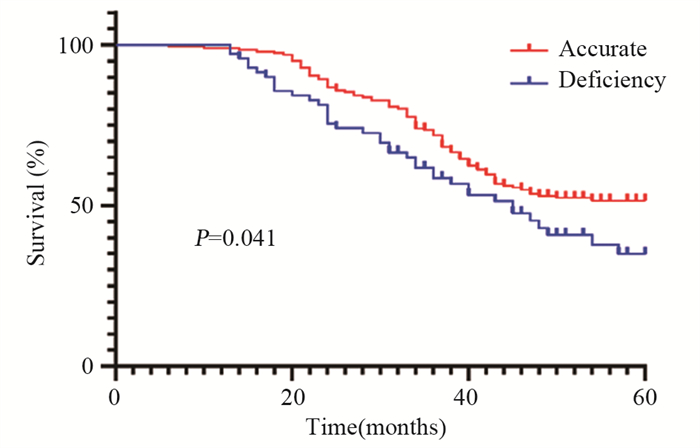

结果年龄、BMI、低分化、Lauren分型为弥漫型是胃癌术前N分期不足的独立危险因素(P < 0.05)。术前N分期不足组预后生存显著差于准确组(P=0.041)。预测模型的ROC曲线AUC为0.935,敏感度为85.9%,特异性为96.9%。

ResultsAge, BMI, poor differentiation, and Lauren's classification as diffuse were independent risk factors for preoperative N-stage deficiency in gastric cancer (P < 0.05). Prognostic survival was significantly worse in the preoperative N stage-inadequate group than that in the accurate group (P=0.041). The AUC area was 0.935, with a sensitivity of 85.9% and specificity of 96.9%.